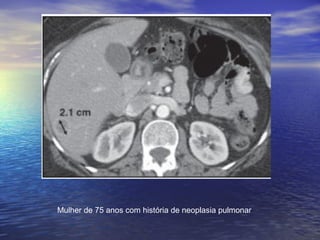

Mulher de 75 anos com história de neoplasia pulmonar